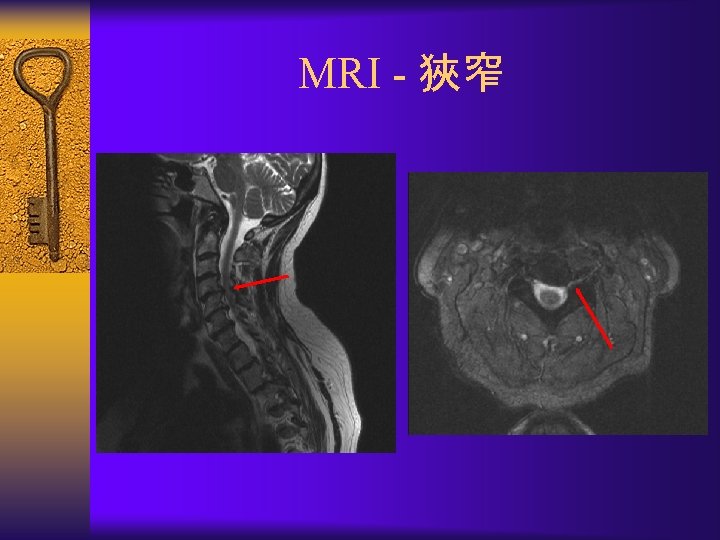

脊椎圓盤退化- MRI ¨ Black disc